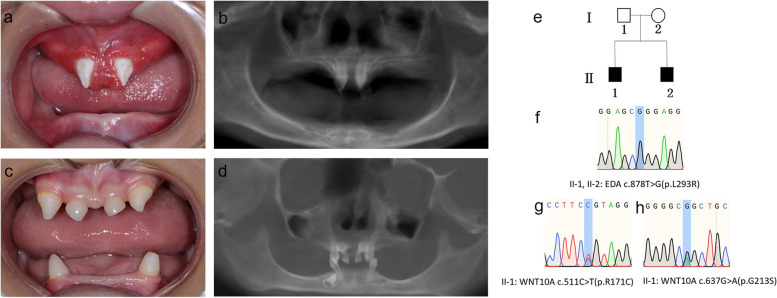

兩名分別為11歲和8歲的親兄弟因先天性牙齒缺失被轉(zhuǎn)診至同佳學(xué)基因具有合作關(guān)系的武漢大學(xué)口腔中心就診。經(jīng)患兒母親及兩名患兒本人簽署知情同意書后,醫(yī)護人員收集了兩位患兒的病史資料,拍攝了相關(guān)臨床照片,并采集了外周靜脈血樣本外送到佳學(xué)基因檢測進(jìn)行致病基因鑒定基因解碼分析。這對兄弟被診斷為低汗性外胚層發(fā)育不良(HED),均表現(xiàn)出典型的臨床特征,包括少牙(hypodontia)、毛發(fā)稀疏(hypotrichosis)、少汗(hypohidrosis)以及面部發(fā)育異常(facial dysmorphism)。有趣的是,哥哥的牙齒發(fā)育不全明顯比弟弟更為嚴(yán)重。哥哥下頜完全無牙,僅保留上頜兩顆中切牙;而弟弟則仍有部分前牙萌出。

體格檢查顯示,這對兄弟均表現(xiàn)出頭發(fā)稀疏、牙齒缺失及汗腺發(fā)育不良(圖1a-d)。兩人均具有X連鎖低汗性外胚層發(fā)育不良(HED)的典型面容特征:鞍鼻、嘴唇厚大、下頜尖翹以及眼周黑眼圈。

口腔檢查及錐形束CT(CBCT)掃描結(jié)果提示,哥哥(II-1)的所有乳牙及大多數(shù)恒牙均先天缺失,僅保留兩顆錐形上中切牙(#11、21)(圖1a-b)。由于下頜牙列完全缺失,他無法正常咀嚼或建立咬合關(guān)系。

弟弟(II-2)尚保留6顆乳牙(#51、53、61、63、73、83)及3顆恒牙胚(#11、21、43)(圖1c-d)。

結(jié)合全身癥狀和口腔表現(xiàn),最終確認(rèn)兩位患兒均診斷為HED。

Fig. 1

圖1:HED兄弟患者的牙齒特征與面部表現(xiàn)

a-b:**兄長(II-1)**的口腔狀況及全景X線片。

c-d:弟弟(II-2)的口腔狀況及全景X線片。

e:家系圖,黑色方塊代表HED患者。

f:DNA測序圖譜顯示兩位兄弟(II-1,II-2)攜帶

EDA基因雜合變異c.878T>G(p.L293R)

g-h:兄長(II-1)同時攜帶兩個WNT10A基因雜合變異:c.511C>T(p.R171C)和 c.637G>A(p.G213S)。

在兩兄弟中均檢測到EDA基因c.878T>G(p.L293R)的錯義變異,但復(fù)合雜合型WNT10A基因變異(c.511C>T(p.R171C)和c.637G>A(p.G213S))僅在兄長中發(fā)現(xiàn)。

母親臨床表型正常,未出現(xiàn)毛發(fā)、汗腺或牙齒相關(guān)異常。WES檢測顯示其為EDA基因c.878T>G雜合變異及WNT10A基因c.511C>T雜合變異的攜帶者。上述結(jié)果均經(jīng)Sanger測序驗證(圖1e-h)。